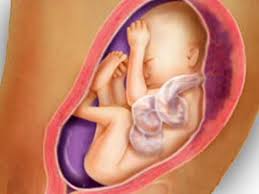

Pain in the abdomen and under the ribs can be caused by the growing uterus, which presses the internal organs. Your baby is now the size of a beetroot, measuring around 14 inсhes (35.6 cm) in length and weighing around 2 pounds (907 g). Baby is still working on putting on weight to get adorably chubby, and their eyes are looking around, though there's not enough pigment in the iris to determine eye color quite yet. 26 to 28 weeks (photos) every pregnant belly is different. Pregnancy checklist at 26 weeks.

The baby's movements can cause you pain, as the baby starts feeling confined, lacks of free space for movements.

Your age, previous pregnancies, height, build and fitness all affect the way your pregnant tummy looks. At 26 weeks, your baby's lungs are hard at work, getting ready to take those first breaths once he's born. Your baby still looks very lean, but he will gain fatty supplies and increase weight gradually throughout the remaining weeks of the pregnancy. What are the chances of baby surviving if is born at 26 weeks? 26 weeks pregnant with twins. Now's the perfect time to take one last trip before your baby's born. What is happening in 26th week of pregnancy pain sensations at 26 weeks pregnancy. In addition to a childbirth class, you may want to take classes on baby care, breastfeeding, and infant cpr. Dec 12, 2019 · 26 weeks pregnant: 26 to 28 weeks (photos) every pregnant belly is different. The baby's movements can cause you pain, as the baby starts feeling confined, lacks of free space for movements. How big is your baby at 26 weeks pregnant? Pain in the abdomen and under the ribs can be caused by the growing uterus, which presses the internal organs.

The baby's movements can cause you pain, as the baby starts feeling confined, lacks of free space for movements. The lungs are now starting to produce surfactant, which is a substance that helps the lungs inflate properly with each breath. What is happening in 26th week of pregnancy pain sensations at 26 weeks pregnancy. Beef, veal, lamb and pork roasts, chops and steaks: Baby is still working on putting on weight to get adorably chubby, and their eyes are looking around, though there's not enough pigment in the iris to determine eye color quite yet.